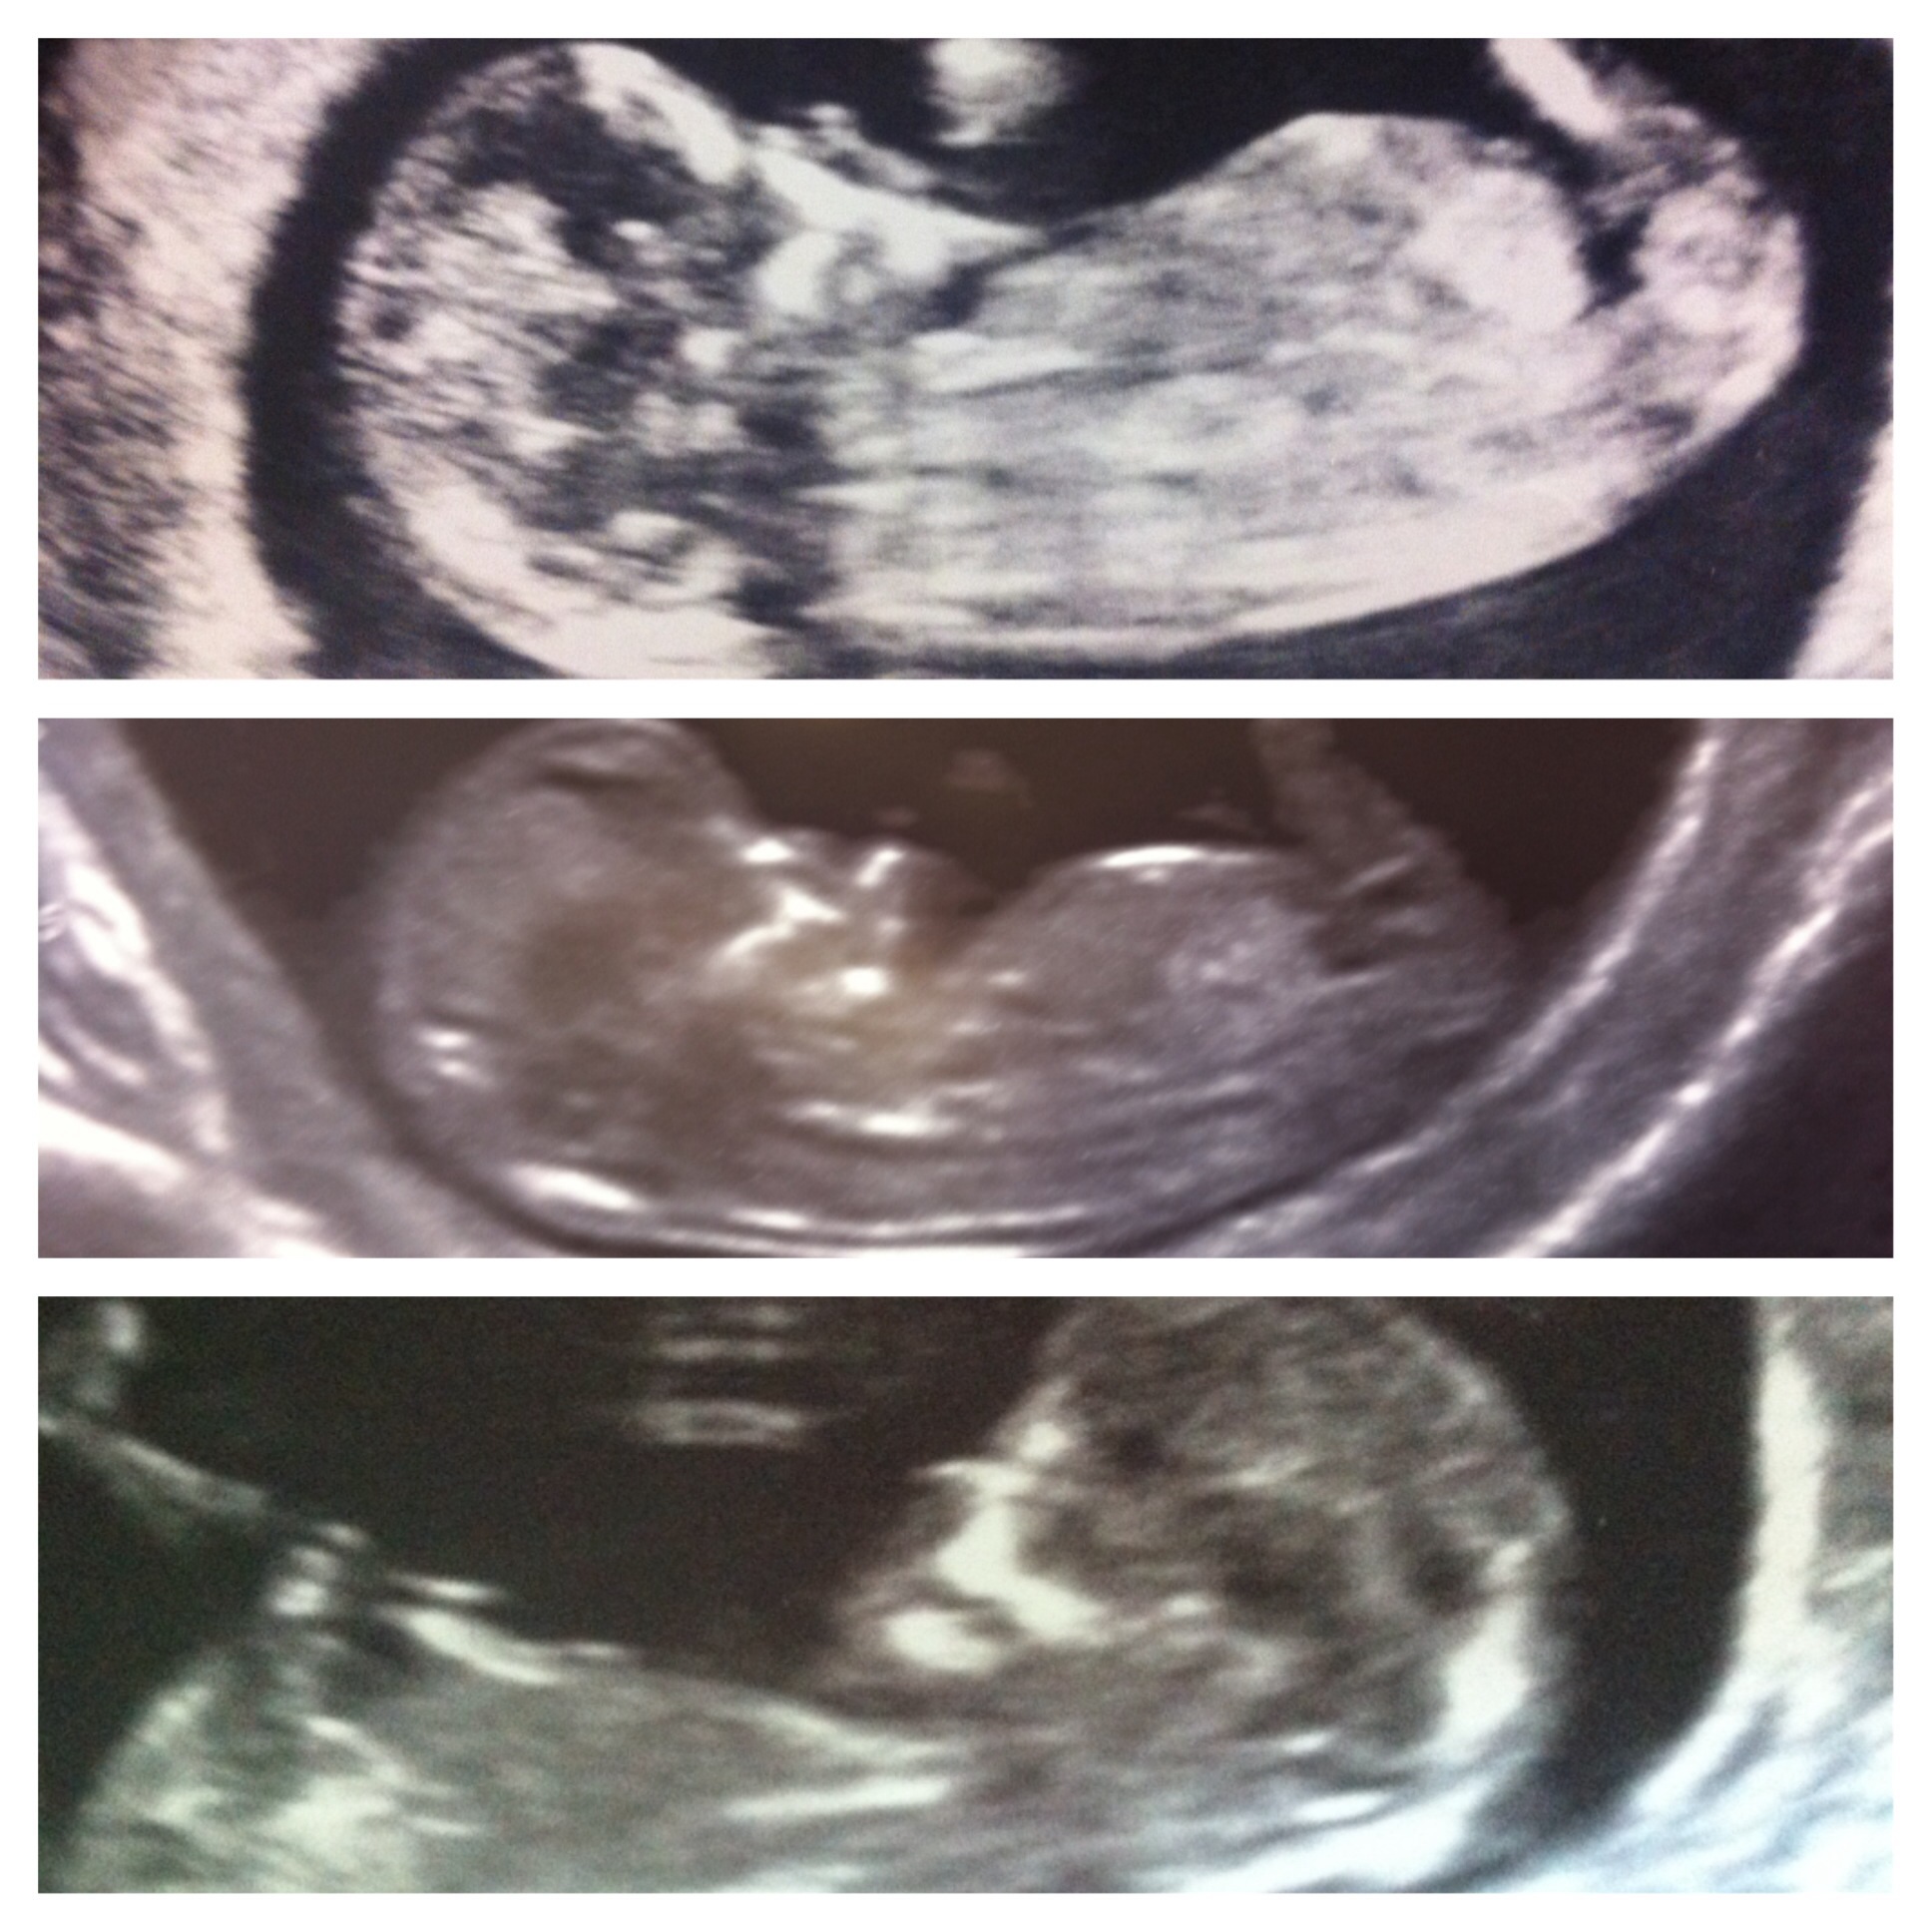

Top 2 are my first and second children, last one is baby I'm pregnant with now x

I'm thinking girl, girl (not as certain on that one), boy. Although looking again, not sure the third you can see the nub.

That's interesting you think the third one is a different gender! The top 2 are boys and I don't know the bottom one yet, there's no nub x

I would say girl, boy, and don't see a nub in last pic. :)

hi based on skull theory all are boys have flat forehead x

As my first 2 are boys seeing if people think the last one is the same x